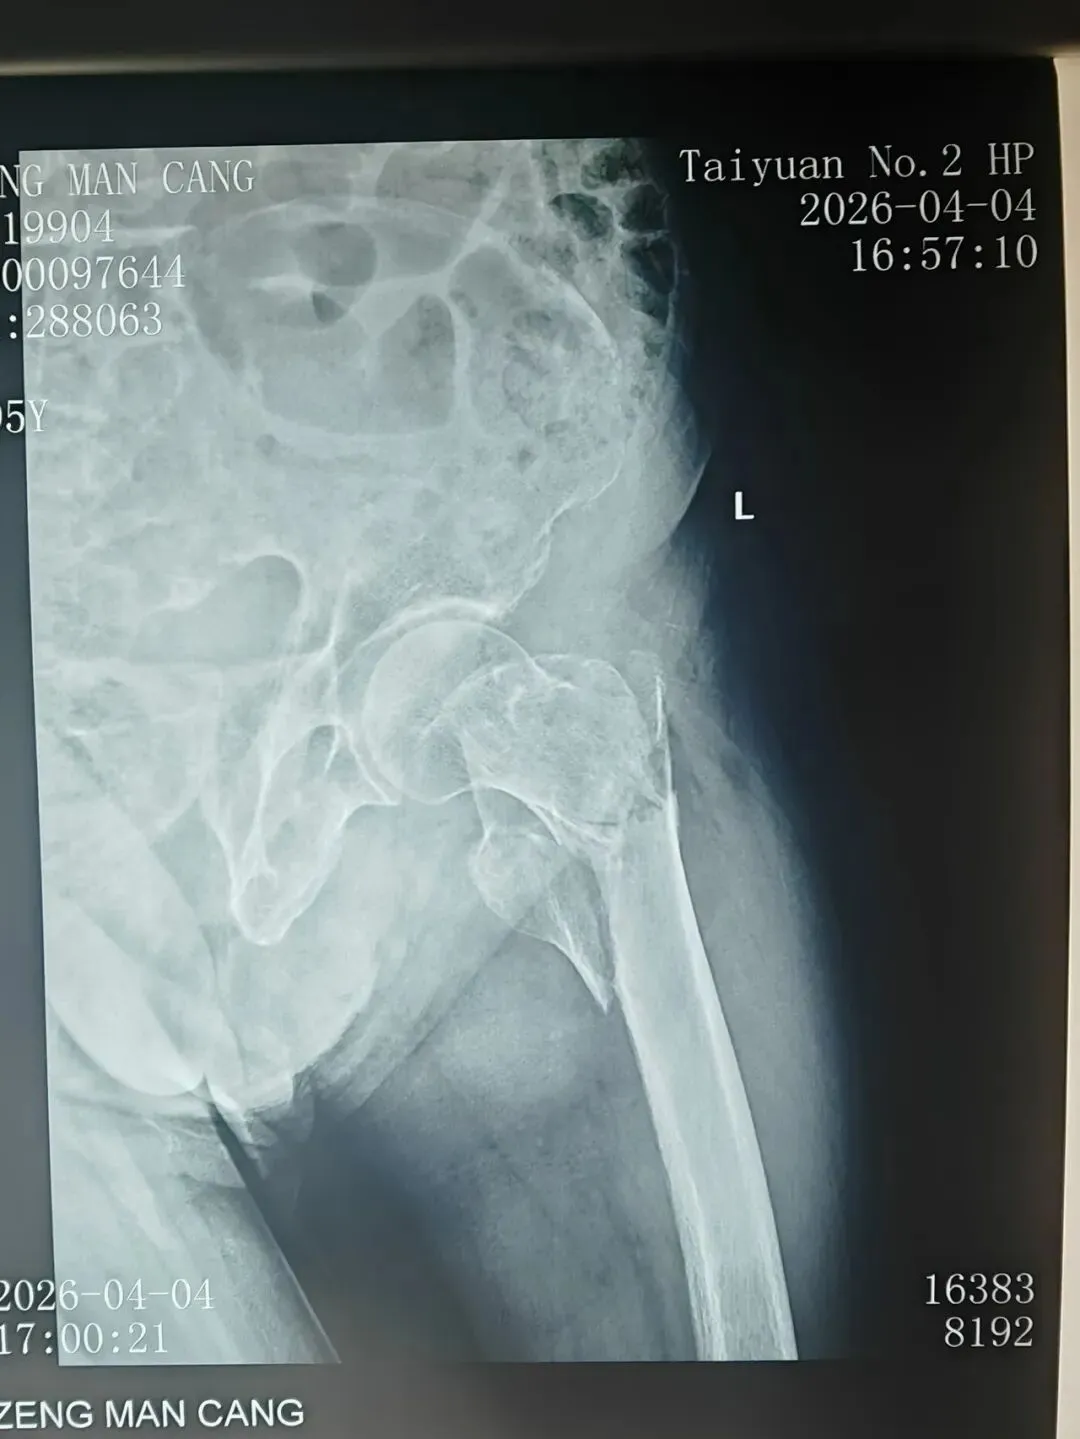

目前,患者确诊为"左股骨粗隆间粉碎骨折”,患者高龄,骨折粉碎性,分离移位明显,手术高难度,高风险。骨科团队考虑到患者年近百岁,身体机能退化,手术耐受性差,存在较高的手术风险。立即启动多学科协作诊疗模式,协调麻醉科,老年病科,检验科等相关科室专家进行紧急会诊,全面评估患者身体状况及手术风险。

术  前